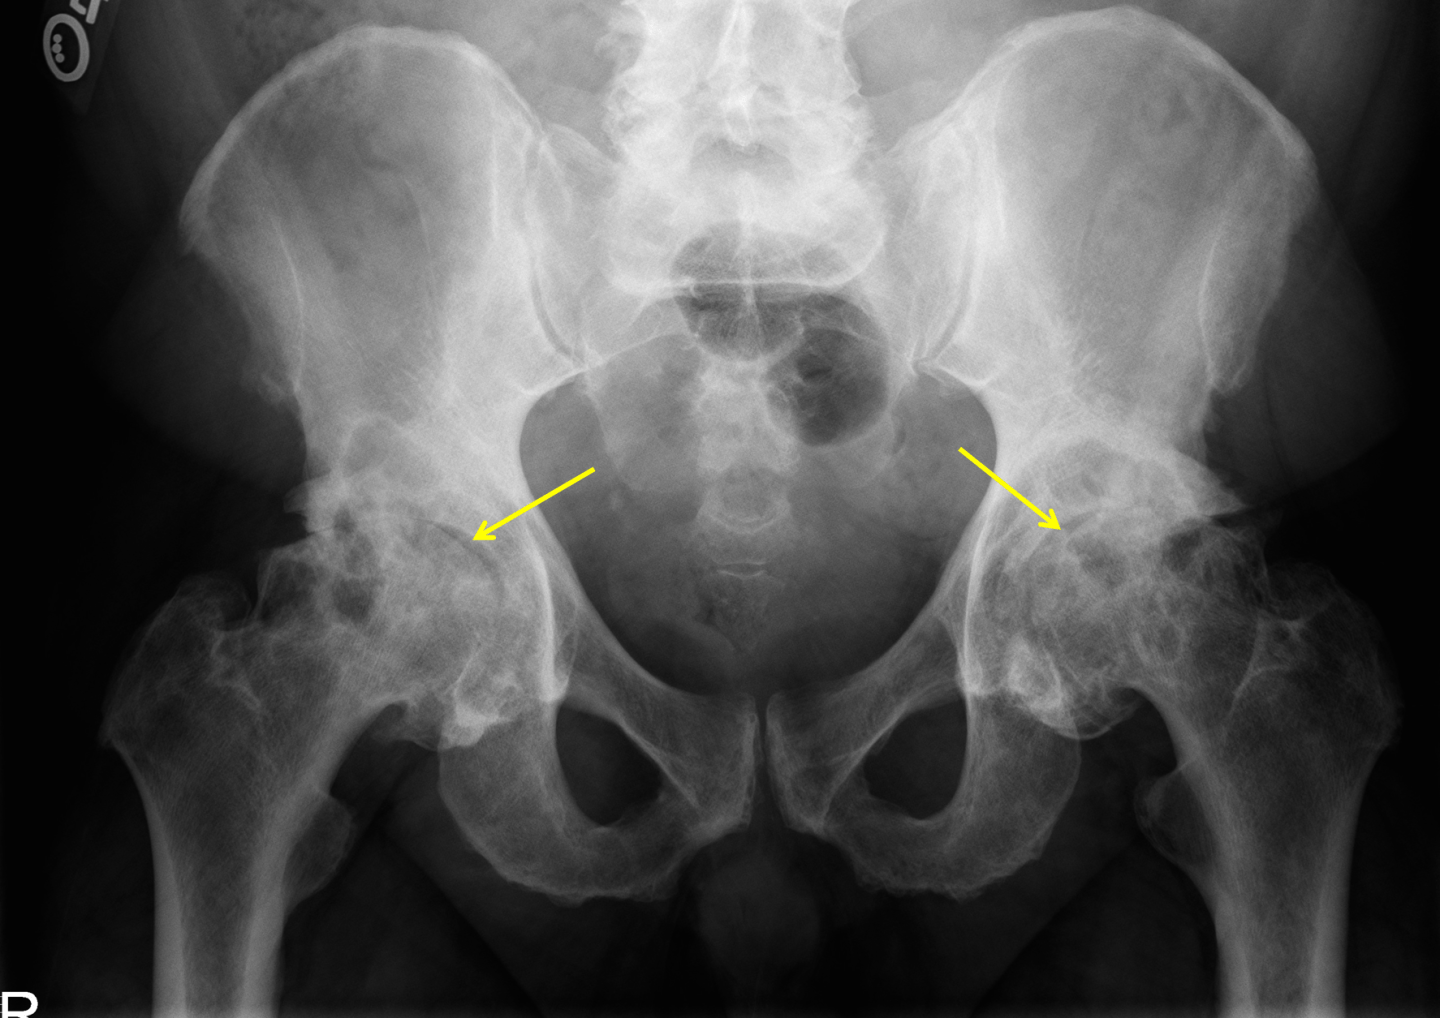

Purpose: To identify patients likely to be presenting with hip osteoarthritis.

Stage of CPR Development: Derivation.

Rule:

1. Squatting as aggravating factor

2. (+) Scour Test for groin or lateral hip pain

3. Active hip flexion causing lateral hip pain

4. Passve internal rotation < 25 degrees

5. Active hip extension causing hip pain

Interpretation:

| Variables | Sensitivity | Specificity | +LR | -LR | Post-Test Prob |

| 1 | 0.95 | 0.18 | 1.20 | 0.27 | 33.0% |

| 2 | 0.81 | 0.61 | 2.10 | 0.31 | 46.0% |

| 3 | 0.71 | 0.86 | 5.20 | 0.33 | 68.0% |

| 4 | 0.48 | 0.98 | 24.30 | 0.53 | 91.0% |

| 5 | 0.14 | 0.98 | 7.30 | 0.87 | 75.0% |

Research:

1. Sutlive TG, et al. Development of a clinical prediction rule for diagnosing hip osteoarthritis in individuals with unilateral hip pain. Journal of Orthopaedic & Sports Physical Therapy. 2008; 38(9): 542-550.